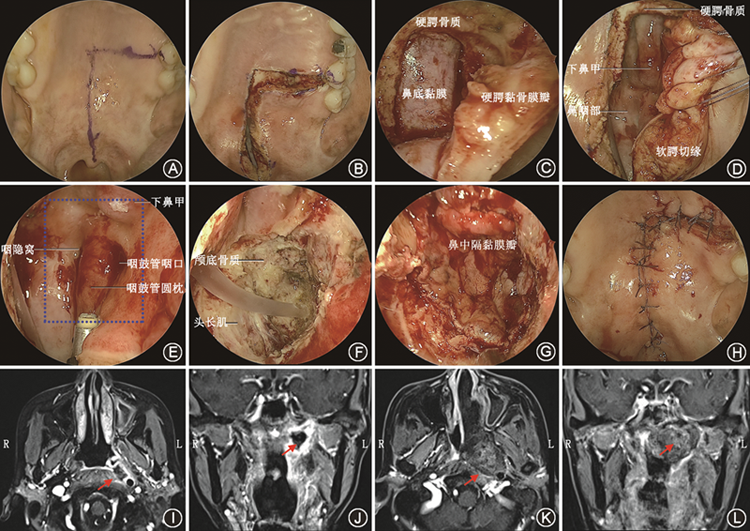

内镜经口侧颅底手术主要通过口腔宽大的自然通道到达侧颅底并处理侧颅底病变。腭构成固有口腔的顶,分隔鼻腔及口腔,经口入路做硬腭黏骨膜瓣时,应注意保护软腭、硬腭黏骨膜瓣的血供。侧颅底各分区解剖复杂,经口入路视角(图2)与颞下窝入路有所区别,熟悉内镜经口入路下的解剖结构是开展内镜经口侧颅底手术的前提。

1. 鼻咽区:鼻咽区位于颅底中央,以咽颅底筋膜在颅底的附着线为界,外侧为咽隐窝。侧方沿翼内板移行至颈动脉管底壁,后达枕骨髁及枕大孔前缘。

2. 咽鼓管区:位于鼻咽外侧,为咽鼓管、腭帆提肌和腭帆张肌在颅底的附着区域,前为翼突基部构成的舟状窝。颞骨岩部呈锥形,位于蝶骨和枕骨之间,斜向前内方,构成颅底的一部分。颞骨岩部前缘与蝶骨大翼连接处的裂隙称为岩蝶裂,咽鼓管由岩蝶裂向后外延伸。

3. 神经血管区:在咽鼓管区后方,由颈内动脉管外口、颈静脉孔、舌下神经孔和茎乳孔共4个颅底孔道构成。经颞骨岩部的颈动脉管外口进入颈动脉管。内镜经口入路中,可借助咽鼓管和腭帆提肌定位颈动脉管外口。

4. 听区:为颞骨鼓部,后界为茎突,前界为岩鼓裂。岩鼓裂有鼓索神经和鼓前动脉穿过。

5. 关节区:以颞下颌关节囊附着线为界,囊内有下颌骨髁状突。颞下颌关节由下颌头与颞骨下颌窝和关节结节组成,左右合成一联合关节,主理张口闭口和咀嚼运动。关节囊松弛,侧方为内、外侧韧带所加强。

6. 颞下区:位于咽鼓管区和关节区之间,其上相当颅中窝,前为眶下裂,外为颞下嵴,内界为茎突,区内有卵圆孔和棘孔,棘孔后为蝶棘。

单纯内镜经口显露颅底的范围有限,通过软腭悬吊可增加鼻咽的显露范围。软腭悬吊后,内镜经口入路上方可显露后鼻孔,下方可显露第二颈椎水平,可处理局限于中线颅底的病变,例如rT1期的复发性鼻咽癌、较局限的脊索瘤等。为了扩大颅底的显露范围,往往需要增加额外的切口。按切口的位置来分,经口入路可以分为中线的内镜经口经腭入路、侧方的内镜经口经翼下颌皱襞入路,以及中线联合侧方的内镜经口经翼突后入路。

1. 内镜经口经腭入路(中线入路):内镜经口经腭入路适用于病变主体位于颅底中线鼻咽区的病变,是解决颅颈交界区腹侧、脑干、延髓等区域病变的经典入路(图3、4)。为了保护腭大动脉、保证皮瓣有足够的血供,显露单侧鼻颅底结构可做“┐”或“┌”形切口(图3),显露双侧鼻颅底结构可做“T”形切口(图4)。切开软腭和硬腭黏膜,掀起软腭、硬腭黏骨膜瓣,可进入鼻咽区,进而显露斜坡及其周围结构,向两侧可拓展至咽鼓管区和神经血管区。